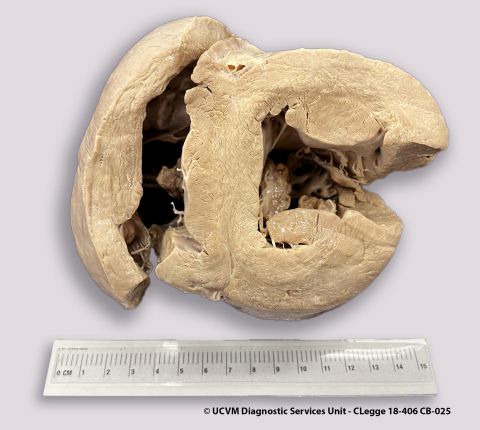

Species: Equid, Horse

Heart, AV valve

Vegetative valvular endocarditis

Irregular yellow-red or yellow-gray vegetations on the valve leaflets, with underlying ulcerations